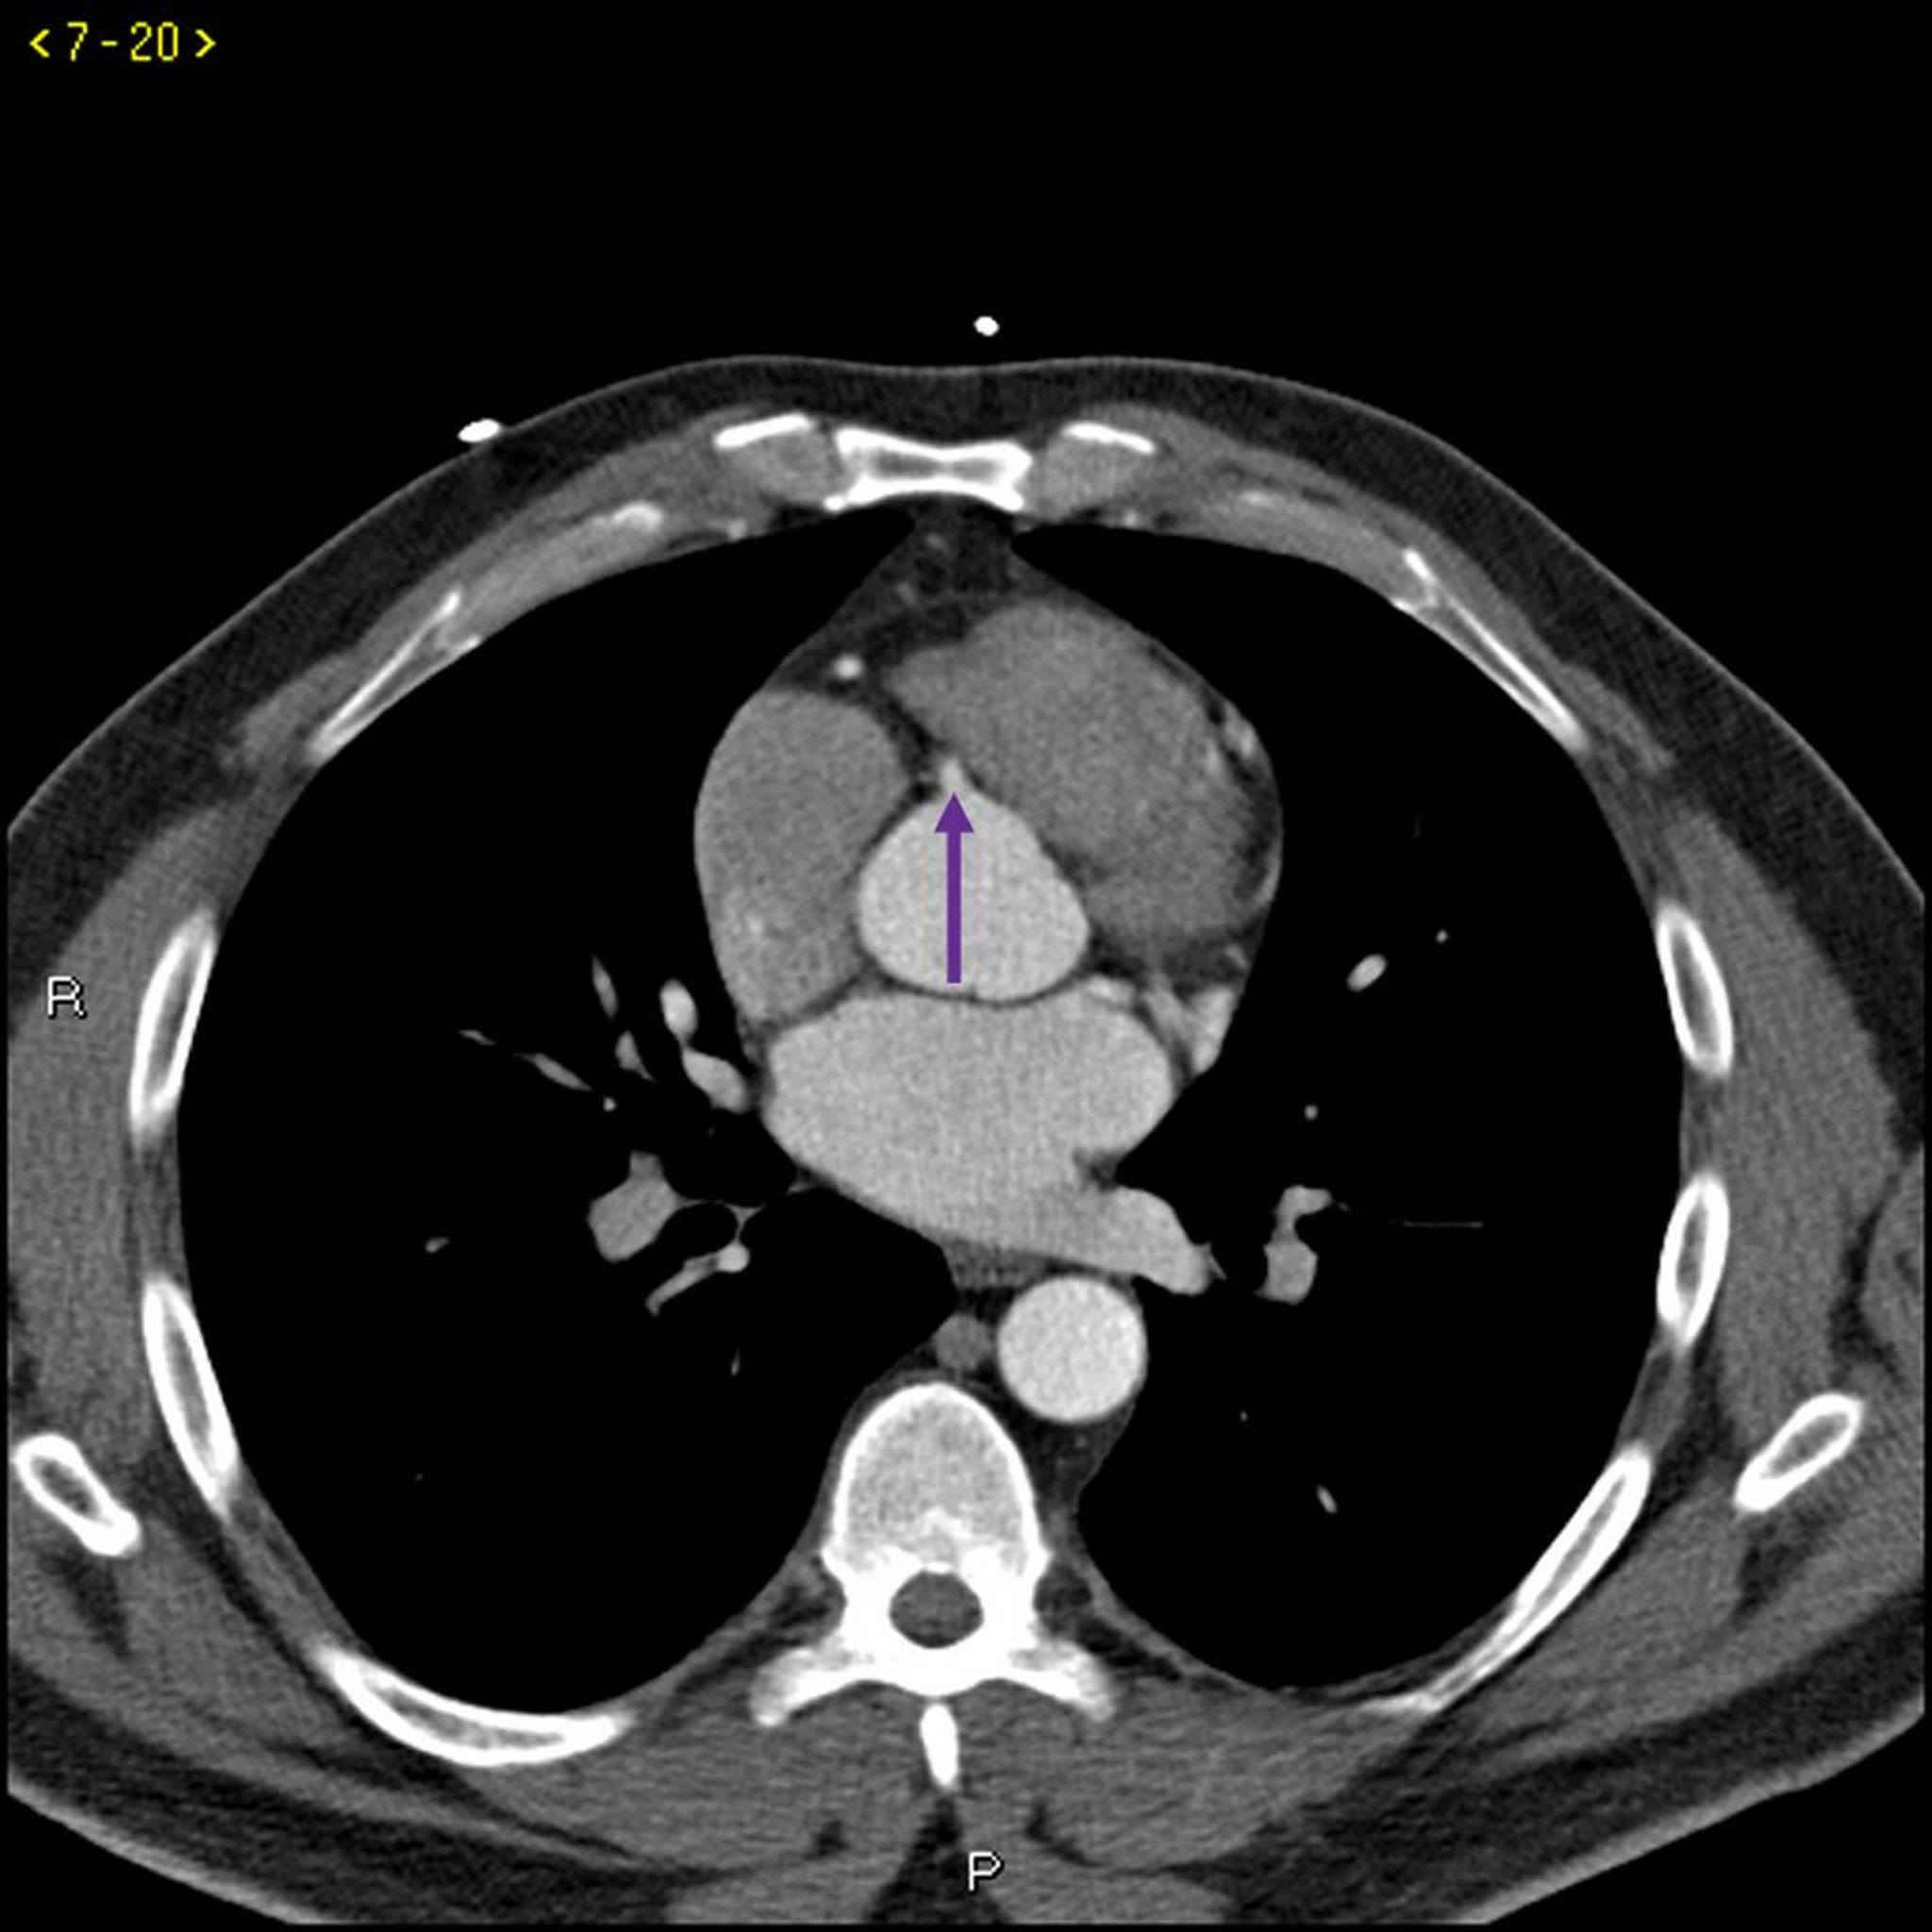

Tomografía computarizada con contraste que muestra arterias coronarias normales–diapositiva 5

Esta TC con contraste muestra arterias coronarias normales. La arteria principal izquierda está indicada por la flecha roja. Las arterias descendente anterior izquierda y circunfleja izquierda están indicadas por las flechas verde y azul respectivamente, y la arteria coronaria derecha está indicada por la flecha púrpura.